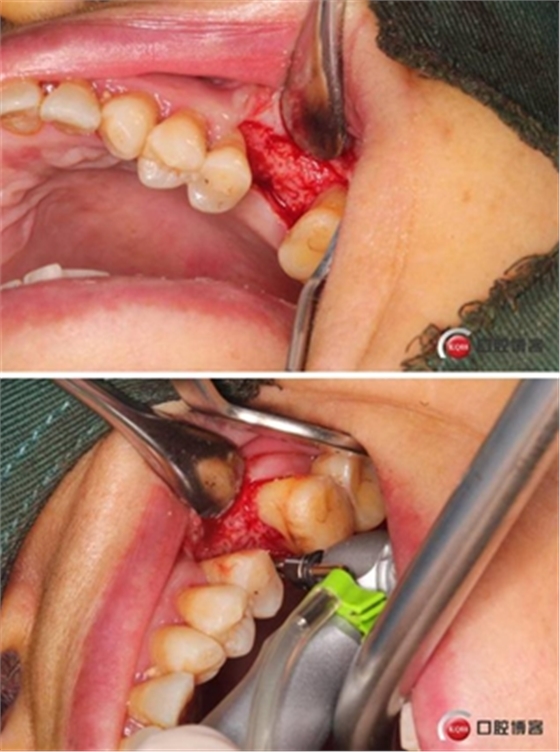

大家好,我是梁老師的助理小依。由于梁老師每天手術(shù)檔期安排較滿,加上經(jīng)常出差講課,沒有時間整理病例 。為了方便大家更及時的了解梁老師最新手術(shù)動態(tài),以后將由我為大家整理并推送梁老師最新經(jīng)典案例。案例文字旁白少,但圖片會盡量完整展示手術(shù)全過程,供大家學(xué)習(xí)參考。有任何問題,可以留言,梁老師會親自為大家解答。感謝大家對梁老師的支持和關(guān)注!